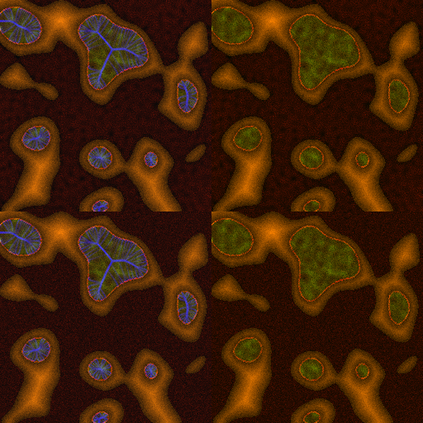

Super-resolution, in-painting, whole-image generation, unpaired style-transfer, and network-constrained image reconstruction each include an aspect of machine-learned image synthesis where the actual ground truth is not known at time of use. It is generally difficult to quantitatively and authoritatively evaluate the quality of synthetic images; however, in mission-critical biomedical scenarios robust evaluation is paramount. In this work, all practical image-to-image comparisons really are relative qualifications, not absolute difference quantifications; and, therefore, meaningful evaluation of generated image quality can be accomplished using the Tversky Index, which is a well-established measure for assessing perceptual similarity. This evaluation procedure is developed and then demonstrated using multiple image data sets, both real and simulated. The main result is that when the subjectivity and intrinsic deficiencies of any feature-encoding choice are put upfront, Tversky's method leads to intuitive results, whereas traditional methods based on summarizing distances in deep feature spaces do not.